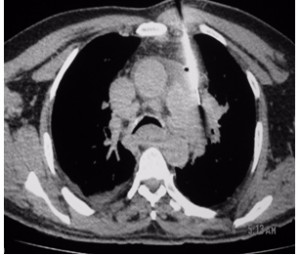

Lesions close to the hilum of the lung like in this case are best biopsied at bronchoscopy. In this case, however, the specimen obtained at bronchoscopy was inconclusive thus forcing a percutaneous biopsy that was only complicated by a small left pneumothorax. I observed the patient overnight in the hospital using periodic chest radiographs and no additional intervention was necessary.